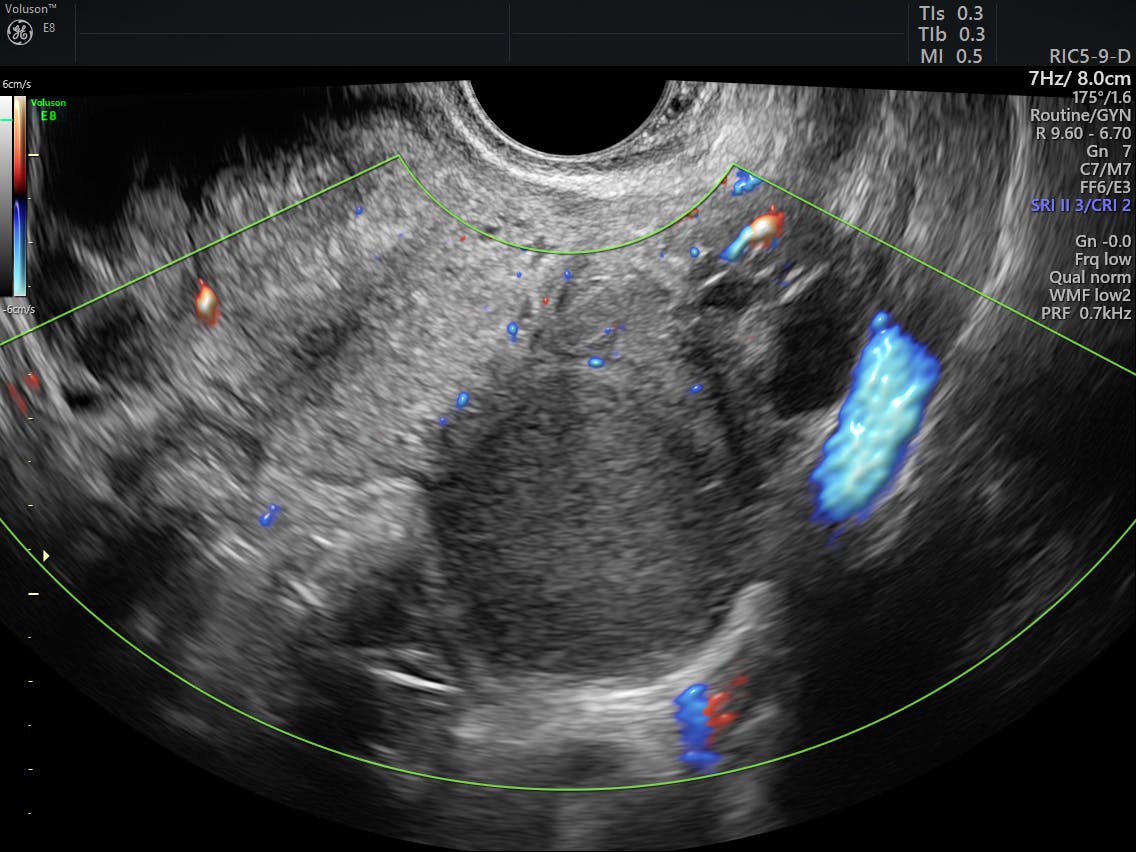

Endometriosis | Lower Abdominal Pain | Period Pain | Ultrasound Care

Source: www.ultrasoundcare.com.au

WebLos síntomas dependen de la ubicación de los implantes. La tríada clásica de síntomas incluye dismenorrea, dispareunia e infertilidad, pero los síntomas también pueden incluir. WebUn dolor de espalda en la zona lumbar puede deberse a la disfunción del útero y ovarios. Aquí te enseñaremos cómo detectar si ese dolor se debe. WebLa endometriosis, definida como la presencia de tejido endometrial –glandular y estromal– fuera de la cavidad uterina, es una enfermedad relativamente frecuente en mujeres. WebEl endometrioma ovárico es frecuente, muy a menudo asociado a otras lesiones endometriósicas de la pelvis. La clínica está dominada por el dolor crónico. WebLa endometriosis es un síndrome bastante doloroso en el cual el tejido que reviste el útero, conocido como endometrio, crece en otras regiones del abdomen como en los ovarios,. WebLa endometriosis es una enfermedad caracterizada por la aparición de trozos de tejido de la capa interna del útero, llamada endometrio, fuera del útero. La. WebDesde 5-10% hasta el 50% de las pacientes con infertilidad o dolor pélvico crónico, 1 de cada 10 mujeres en el mundo durante su vida reproductiva (15-49 años) padecen. WebUn dolor consuetudinario en la parte baja de la espalda puede ser indicio de cáncer de ovario. El cáncer de ovario es el sexto más consuetudinario a caballo entre las mujeres,.

WebEl endometrioma es un quiste ovárico originado por tejido endometrial, el contenido está constituido por un líquido espeso de aspecto denso y de color café muy. WebEndometrosis y adenomiosis, otra causa de dolor abdominal y lumbar. Salud Hormonal ¿Algunas de vosotras tenéis, dolor justo antes de la regla, o durante ella,. WebLos signos clínicos del endometrioma ovárico no son muy diferentes de los de otras localizaciones de la enfermedad. Se observa dismenorrea, dispareunia.